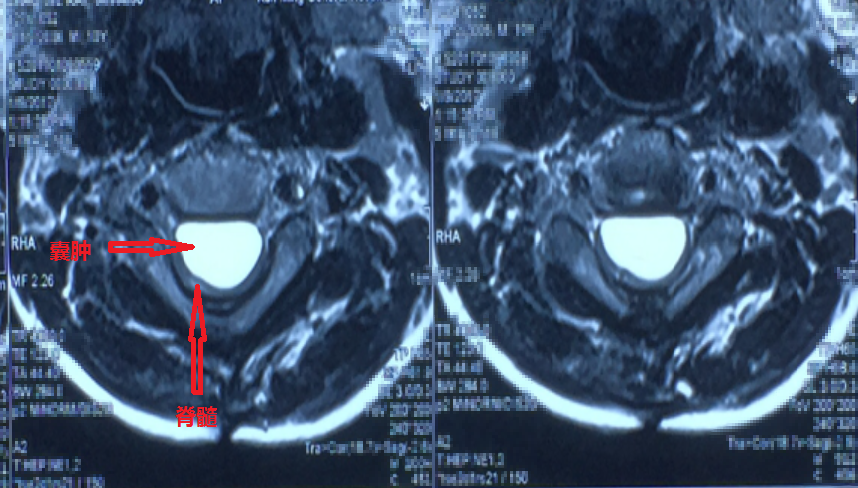

来我院前复查,囊肿(红框内)仍然在,颈椎已出现严重的后凸(反曲)畸形,孩子四肢无力,上肢不能持物,下肢不能行走

脊髓被囊肿压迫得还剩一个薄片